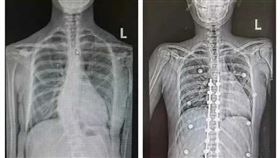

脊椎側彎像蜈蚣!21歲女術後矯正長高8CM

台中一名21歲印尼黃姓女僑生,因嚴重脊椎側彎,導致心...

2025/06/26 16:39